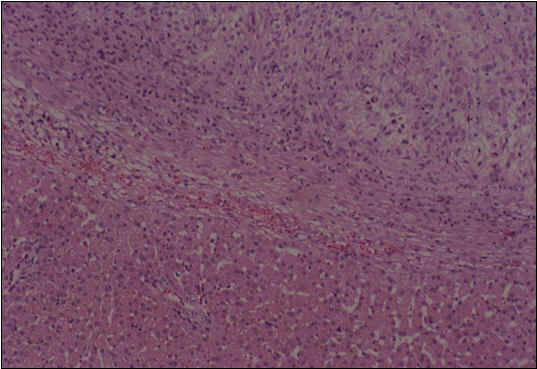

Human Primary colon cancel tissue (X100) preserved using Mebiol Gel - 14 days specimen. Regeneration of Hepatocytes into an area filled with Mebiol gel (Experiment in dogs)